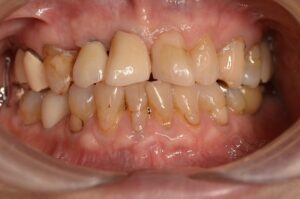

CT撮影すると骨がほとんどありません。

このままではインプラントができませんので骨に変わる材料を補填していきます